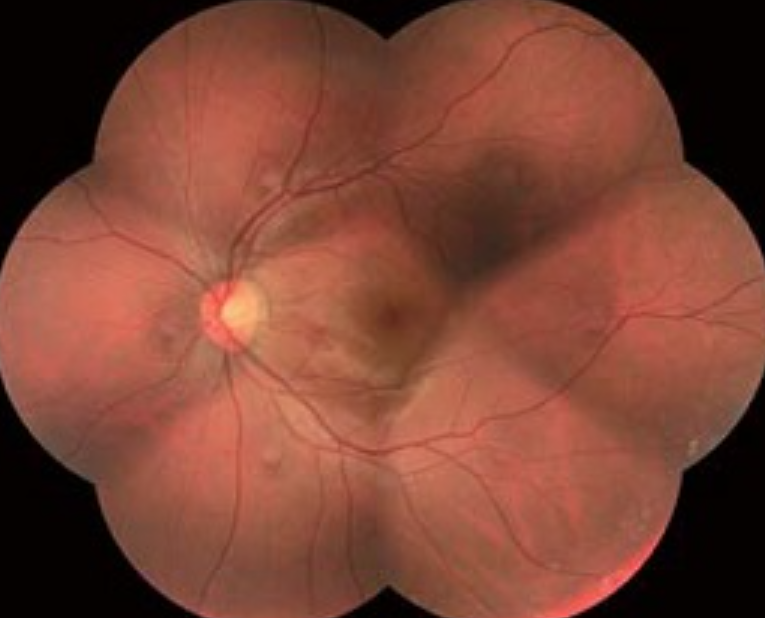

Fundus kamera – Nejnovější nemydriatická kompaktní funduskamera se špičkovou optikou a profesionální CCD kamerou s velkým rozlišením pro snímání sítnice a předního segmentu oka. Slouží ke sledování změn na předním segmentu a sitnici (névy, zrakový nerv, žlutá skvrna aj.)